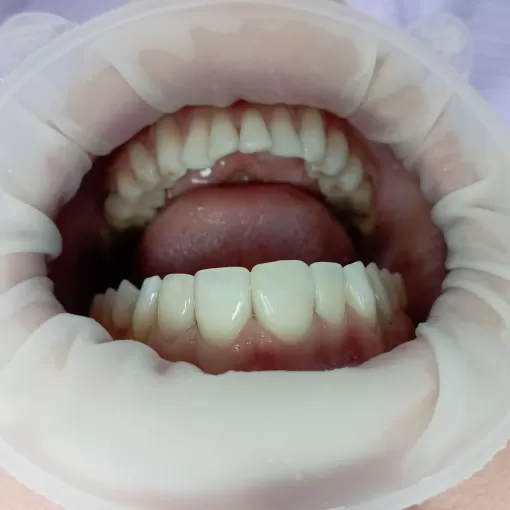

Совместная работа с ортодонтом, после брекет-системы эстетическая реставрация, устранение трем и диастем

Совместная работа с ортодонтом

Эстетическая реставрация 4-х передних зубов